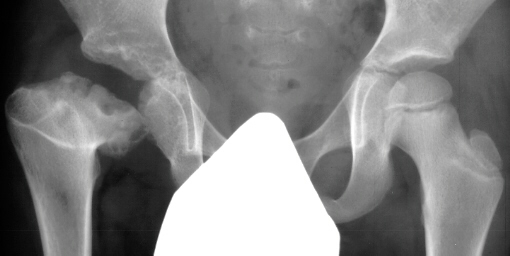

- Post Operative Day 18: R hip Xray: subluxation of R hip, possible metaphyseal

lucency consistent with osteomyelitis. Taken to OR for repeat I & D

Institute. Initial labs: WBC 15,100, ESR 72. R hip Xray: changes in proximal

. metaphysis including lucency and demineralization, hip subluxated. Treated

with oxacillin and Pavlik harness.

- 2 month Office Follow Up: Rt hip Xray: progressive destruction of capital

femoral epiphysis, cystic changes in metaphysis consistent with AVN.

- Age 6: Valgus osteotomy for subluxation and 2cm leg length inequality.

- Age 15: Valgus osteotomy for hip incongruity.

- Age 20: Hip arthroscopy. Hip fusion recommended.

This case is an example of untreated septic arthritis which caused avascular

necrosis of the proximal femur. The primary cause of this is undrained

septic hip. Repeated aspiration is not adequect treatment of a septic hip.